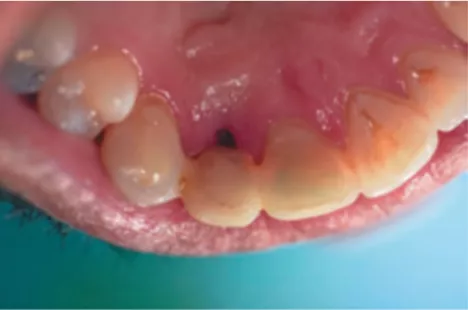

FIG 1:

X-Ray of 36 year old malepatient who had undergone repeated root canal treatment, two apicoectomy procedures and a poorly done stabilisation over the past few years at some other clinic. But there was a fistula with purulent discharge and accompanying pain and inflammation in the region warranting tooth extraction.